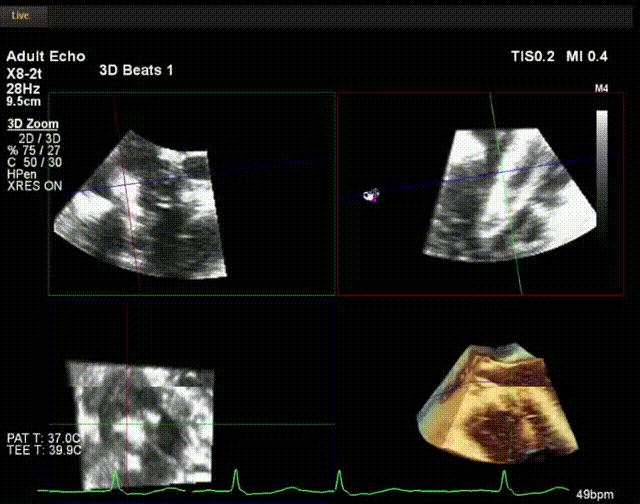

術(shù)中超聲

陸方林教授通過遠程線上帶教的方式,與林逸賢教授團隊共同完成了此次LuX-Valve Plus人工瓣膜的首例植入。術(shù)后食道超聲提示三尖瓣反流完全消失,無瓣周漏,且LuX-Valve Plus人工瓣膜的兩個夾持鍵成功抓取瓣葉,錨定牢固,人工瓣膜穩(wěn)定性良好。

林逸賢教授表示:雖然此次手術(shù)難度大,患者高齡,解剖結(jié)構(gòu)復(fù)雜,但LuX-Valve Plus表現(xiàn)出非常顯著的優(yōu)勢,(1) 操作簡便,器械操作時間短(僅不足30min),器械使用流暢度和容錯率高;(2) LuX-Valve Plus輸送系統(tǒng)調(diào)彎性能好,術(shù)中可進行五維調(diào)整,保證了人工瓣膜良好的同軸性;(3) 術(shù)中對超聲影像的依賴程度低,使用經(jīng)胃底短軸切面,配合右室流入/流出道及X-Plane切面即可相當容易地獲取相關(guān)影像,以快速推進手術(shù)進程。